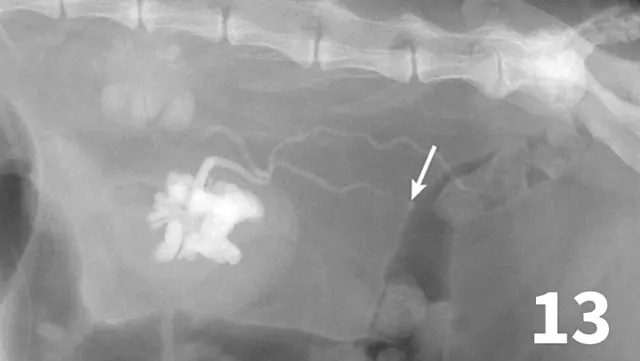

Normal ureters cannot be visualized with survey radiography or ultrasonography, but normal and abnormal ureters are readily visualized with excretory urography. The location of a ureteral obstruction or rupture as well as the presence of an ectopic ureter (especially when combined with pneumocystography) can be documented with excretory urography (Figure 11). A dilated ureter (hydroureter) can be observed with ultrasonography (Figure 12). Pyelocentesis (for cytology and culture) and antegrade pyelography (nephropyelography) (Figure 13) to document obstruction or leakage can be conducted via ultrasound guidance with heavy sedation or anesthesia. Ultrasonography can also be used to visualize retroperitoneal fluid accumulation, which may occur with a ureteral rupture, hemorrhage, or infectious or neoplastic disease. Whereas ureteroliths without hydroureter may be missed on ultrasonography, radiopaque ureteroliths can be observed on survey radiography (Figure 14). Survey radiographic visualization of radiopaque ureteroliths may be facilitated by enemas to empty the colon of fecal material and/or use of a radiolucent paddle to apply regional compression over the ureter to separate adjacent organs (eg, loops of bowel) (Figure 15). Aged cats with chronic kidney disease (CKD) frequently have calcium oxalate nephroliths; in some cases, these nephroliths will migrate into the ureters. Survey radiographs should be employed to rule out ureterolithiasis, especially in cats with acute decompensation of their CKD (Figure 16).